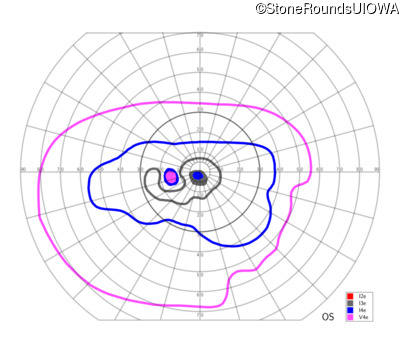

Congenital Stationary Synaptic Dysfunction (IA2g)

Congenital Stationary Synaptic Dysfunction (IA2g)

| Age at visit: 33 years |

| Age at visit: 35 years |

| Age at visit: 37 years |